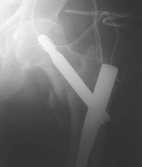

Seitlich wurde der Nagel fehlpositioniert, was

beim Belasten zum Auswandern führte. Mit dem Zielgerät

nach Asche wäre dies nicht passiert.